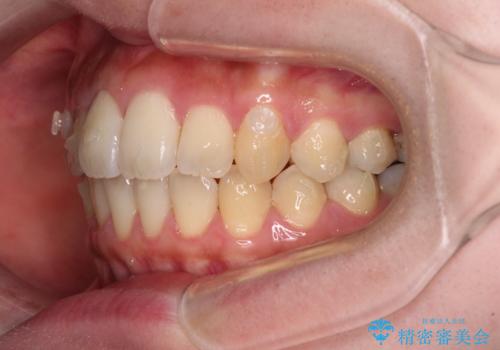

- 捻れた前歯が飛び出しており、口が閉じにくいとのことで来院された患者様です。

出っ歯というわけではないものの、前歯の捻転により口唇が押し出されている状態でした。

親知らずを抜去し、歯列全体を後方に移動させつつ、IPR(歯と歯の間を削る)でスペースを獲得し、インビザラインを用いて叢生を解消しながら前歯の突出を改善することとしました。